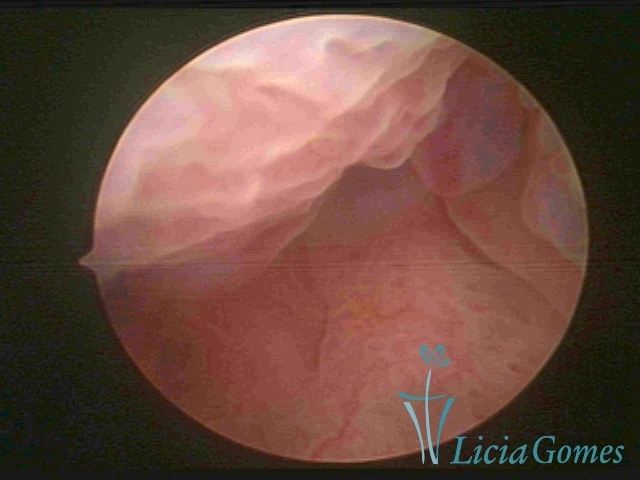

Primeira porção ou setor proximal ou setor inferior:

Durante a fase proliferativa, encontramos muco claro e cristalino pouco aderente à óptica. As criptas e as papilas apresentam-se um pouco edemaciadas e vascularizadas, micro vesicular, lembrando cachos de uva.